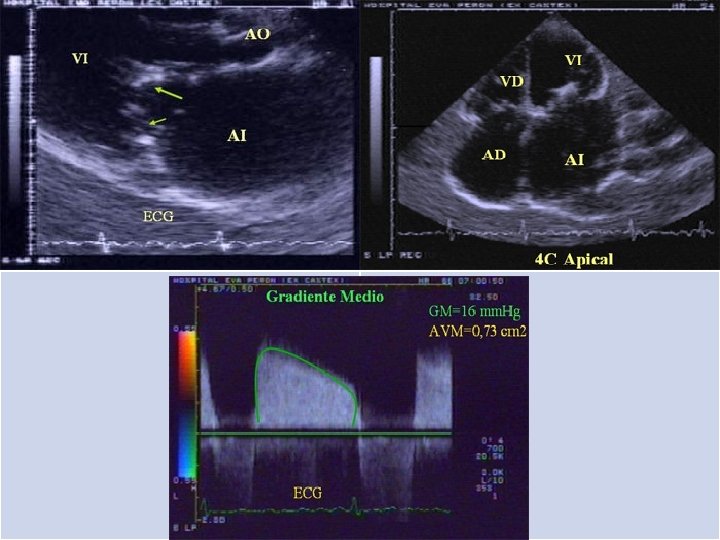

ESTENOSIS MITRAL ECOCARDIOGRAMA: Diametros de cavidades. Morfologia planos valvulares. FEVI. AVM. HAP. “Trombo” AI. Gradiente medio de presión: EM ligera= <7 mm. Hg EM moderada= 7 -14 mm. Hg EM severa= >15 mm. Hg

Graduación de severidad Normal : 6 cm 2. EM leve: cm 2. EM moderada: -1. 5 cm 2. EM severa: área entre 4 área entre 1. 5 -2 área entre 1 área < 1 cm 2.